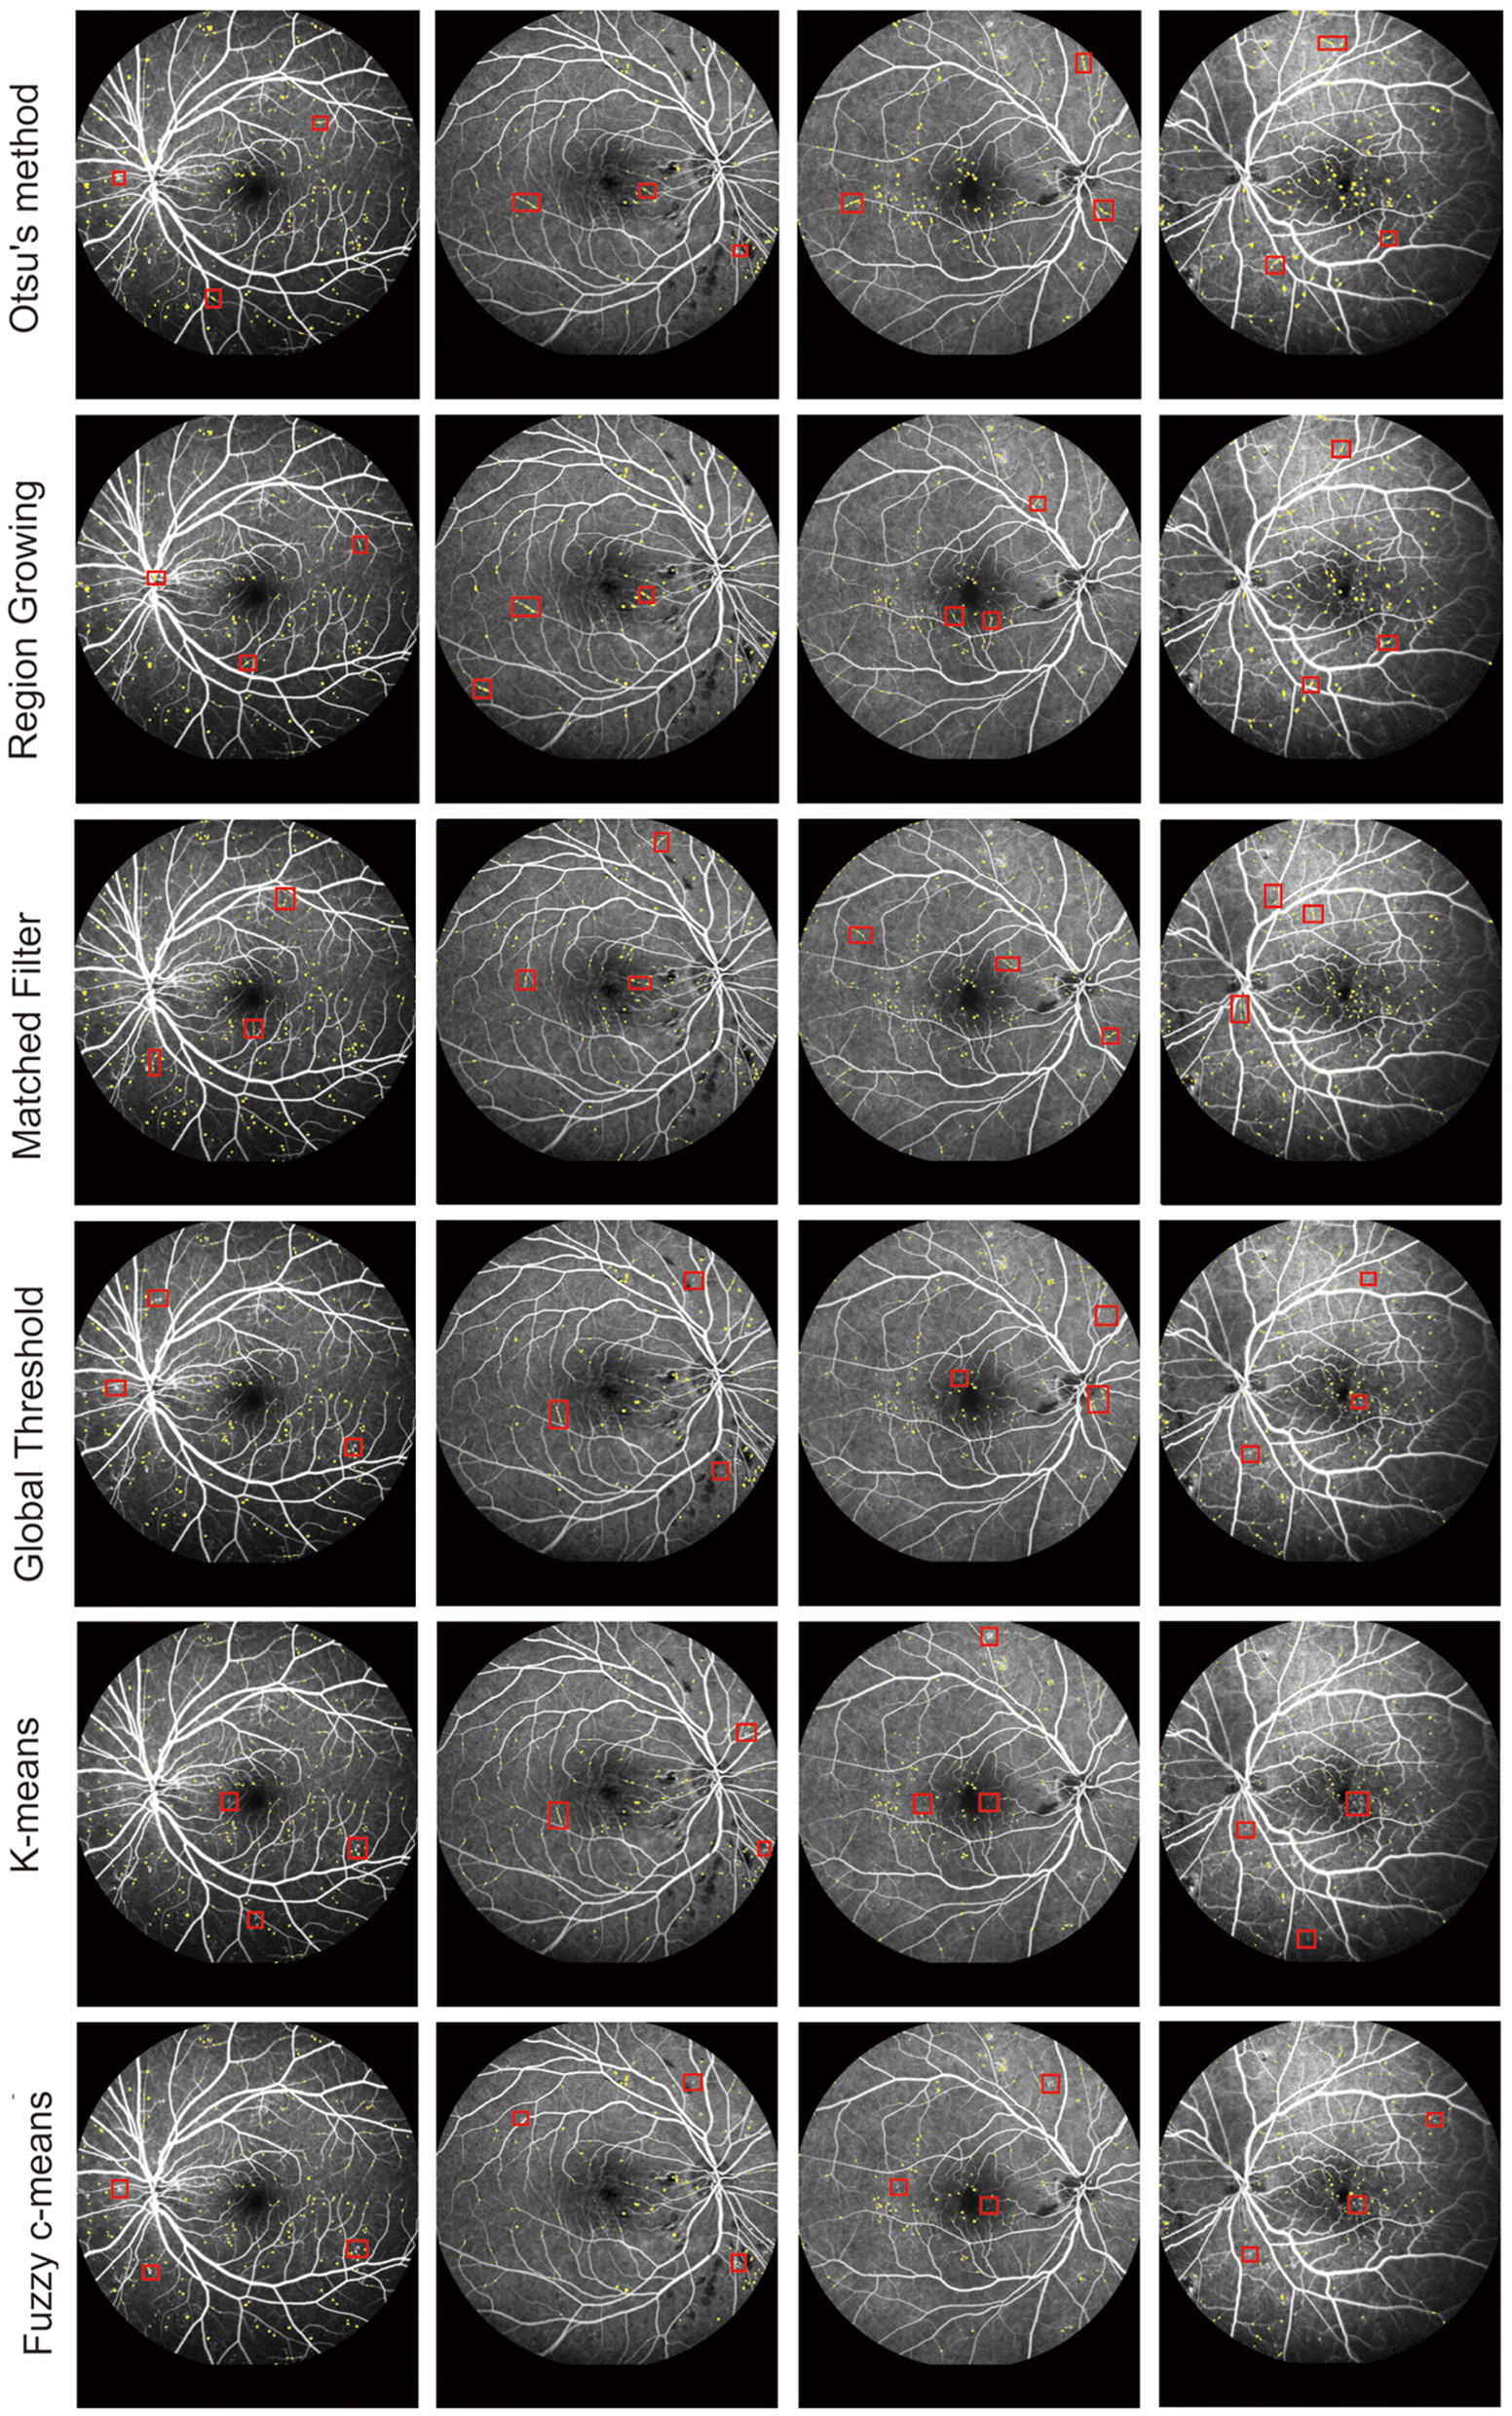

We further compared our proposed model against other MA detection models, such as Otsu's method (33), Region Growing (34), MF (25), Global Threshold (35), K-means, (36) and Fuzzy c-means, (37) to evaluate MA detection performance. The results of MA detection are shown in Figure 4, and the metrics of MA evaluation are shown in Table 2.

Figure 4

MA segmentation results from different models.

As shown in Figure 3 and Table 2, Otsu's method, Region Growing, MF, Global Threshold, K-means, and Fuzzy c-means models could not accurately detect the boundaries of MA regions and normal regions. Additionally, there were some omissions and false detections, which are marked by red squares in Figure 4. The proposed model had greater values of PPV and IOU than other models. Furthermore, our proposed model demonstrated performance in MA detection that closely aligned with the benchmark standard, surpassing the performance of other MA detection models.